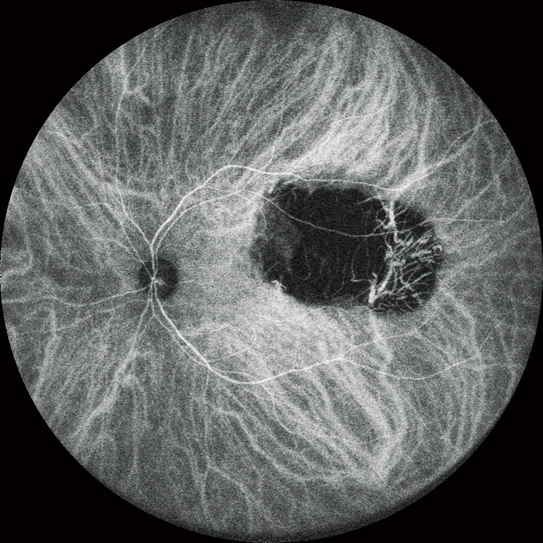

高清動態血管造影

可錄制分辨率高達1,024 x 1,024像素,最長時長為120秒的視頻。在同一次測量中也可分段錄制多個短視頻。

FA和ICG同步血管造影

Mirante操作簡便,可同步拍攝FA和ICG影像。實時IR監測方便操作者在熒光產生前調整拍攝位置,降低錯過血管造影早期階段的風險。

自動增益控制(AGC)可同步調整各個FA和ICG圖像的對比度,使動態血流成像成為一個非常簡便的過程。

* 適用于SLO/OCT型。SLO型可選。

同步FA和ICG成像顯示

實時紅外監控